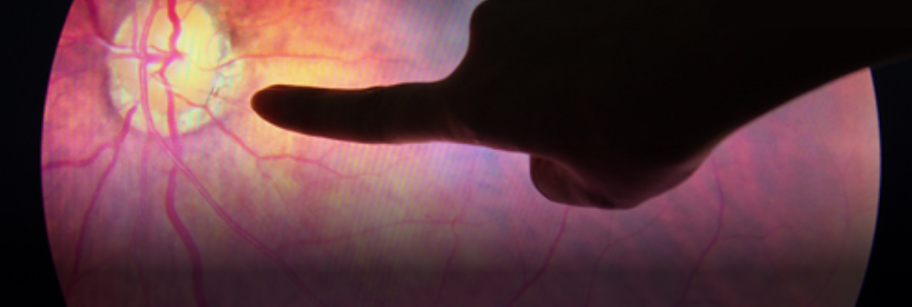

La retina es el tejido nervioso situado en la parte posterior del globo ocular, se encarga de recibir y procesar los estímulos lumínicos que ingresan al ojo, se trata de células nerviosas muy específicas. La falta de oxigeno (isquemia) y las hemorragias (sangrados) dañan las células nerviosas, lo que repercute en la visión.

La retinopatía diabética es consecuencia de la alteración de la microvasculatura retiniana, se producen sangrados, inflamación e isquemia.

El daño producido en el ojo es progresivo, por lo que es muy importante revisar al momento del diagnóstico y periódicamente a los pacientes diabéticos. El examen debe incluir al fondo de ojo, este estudio permite ver la retina y los vasos sanguíneos. En algunos casos conviene realizar también estudios complementarios.